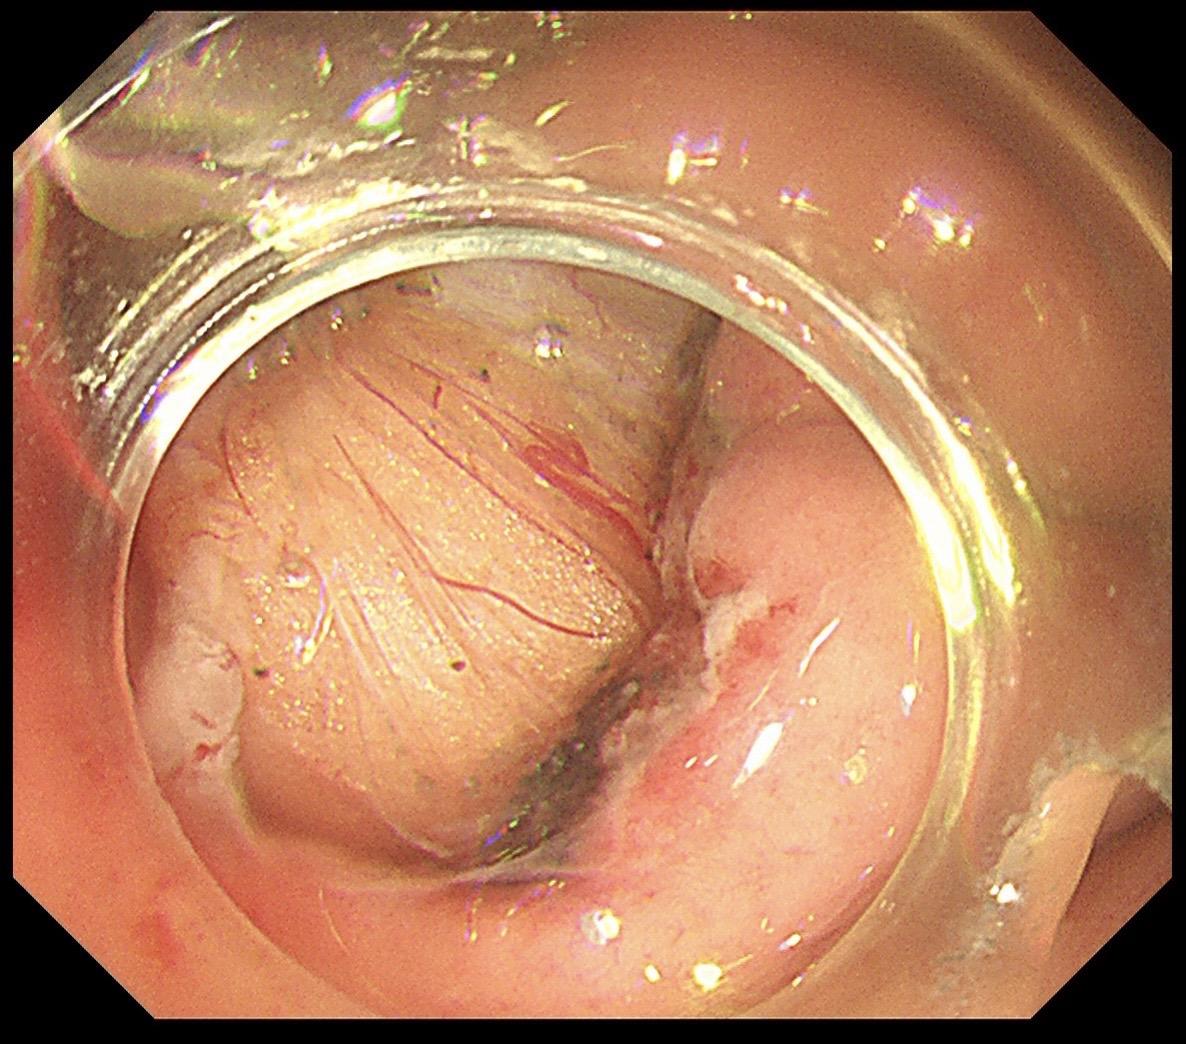

胃黏膜下隆起都是间质瘤吗?不是的!这个很像间质瘤的胃黏膜下隆起,其实是胃壁钙化的结核结节!切胃黏膜下隆起就像开盲盒,病理没出来谁也无法完全确定!